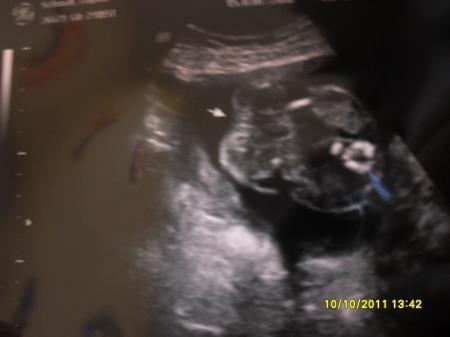

lol da sieht man es eigentlich bei der kleinen , der Arzt hat extra Pfeil drauf gesetzt

Bild zu